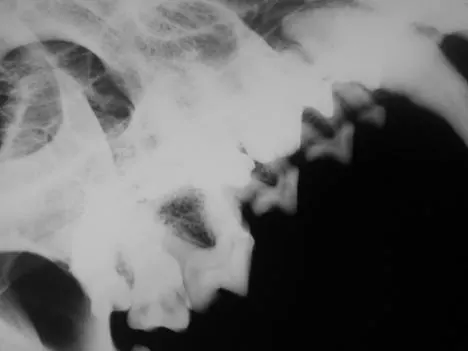

It is less convenient and more technically difficult to obtain high-quality dental images with traditional radiographic techniques. The radiograph machine is usually distant from the dental operatory, making it necessary to move the patient to obtain radiographs. Positioning is more difficult because the tube head is stationary. The need for extraoral film placement increases the difficulty of avoiding overlapping of structures. Dental films placed intraorally can be used with a standard radiographic machine to help with some of these problems; however, the practitioner wishing to incorporate dental radiology into his or her practice is advised to invest in a dedicated dental unit.

Skulls were used for these images. Dental images were obtained with a digital sensor; the traditional radiographs were taken using extraoral technique with a standard radiographic machine.

A radiographic image shows a close-up view of a canine thoracic cavity, highlighting the heart and surrounding structures. The image displays varying densities, indicating the presence of soft tissues and potential abnormalities within the chest area.